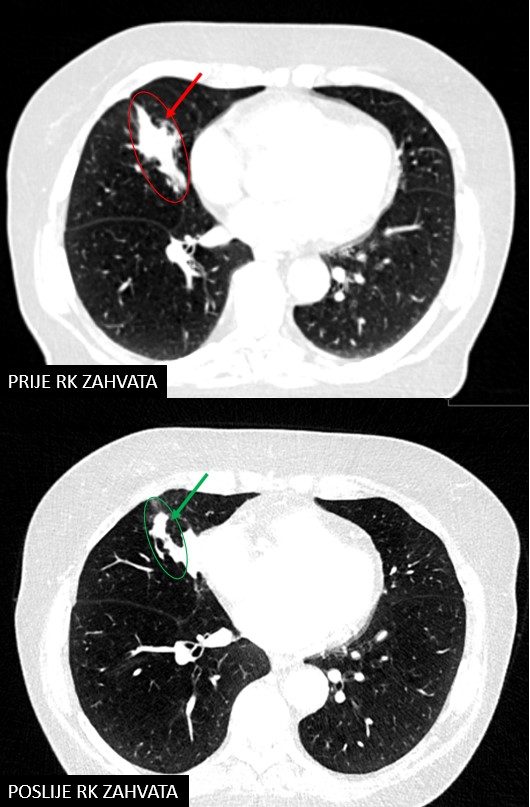

Bolesnica, rođena 1945.

Dijagnoza:

Npl. pulmonis lobi medii lateris dextri (2018.)

SABR npl. pulmonis lateris dextri (06.07.2018.)

Rezultat – 54 mjeseca nakon RK

smanjenje tumora pluća za 38.6 %